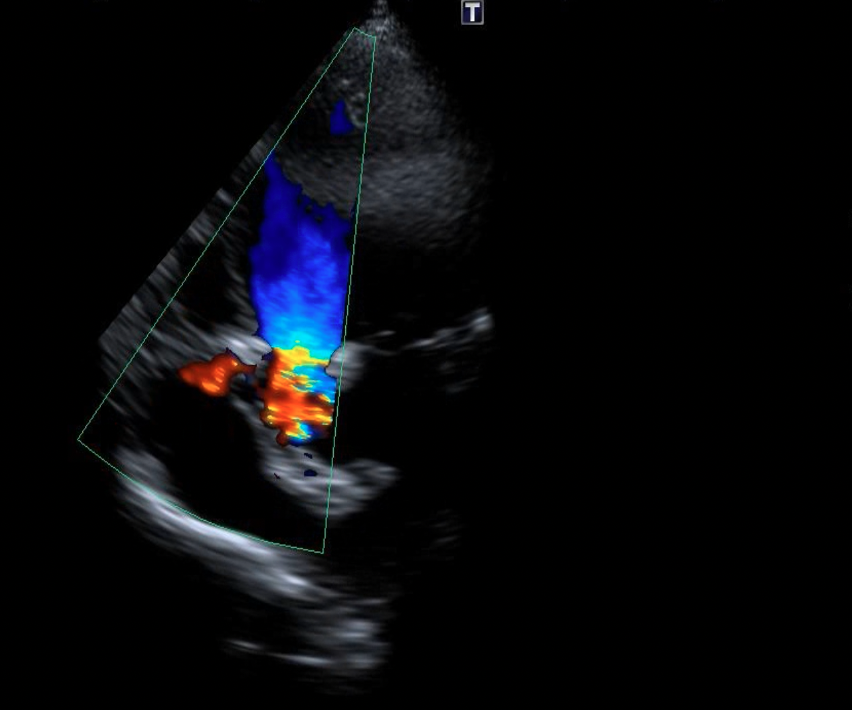

We chose an appropriately sized occluder, which was 20% greater than the entrance diameter of the ruptured SVA. The selected occluder with its attached delivery cable was inserted through the delivery sheath from the venous route, and its aortic disc was deployed in the ascending aorta. Positioning of the device (an ADO single-disc device of 6-8 mm) was then confirmed under transthoracic echocardiography (Figures 4A-C, Videos 4A-C).

Figure 4. (A) Positioning of the Amplatzer Duct Occluder (ADO) device (Abbott) (blue arrow). (B) Transthoracic echocardiography. (C) No residual shunt observed across the defect following device placement on transthoracic echocardiography.

(Figure 4B)